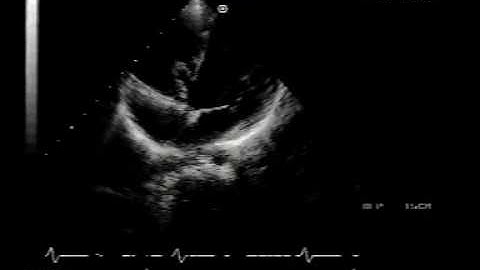

What is a perimembranous VSD? Intro